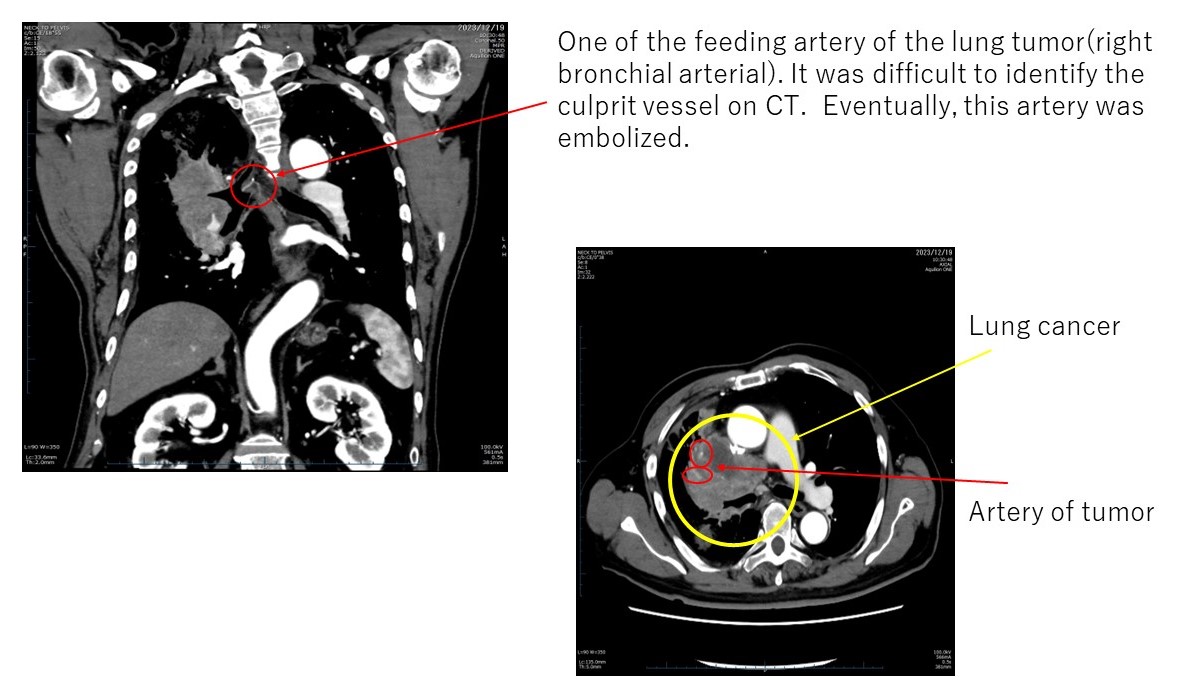

Additionally, Figure 6 delineates the locations of extravasation detected in a patient’s lung cancer as visualized on CT images. Specifically, in panel (b), one of the feeding arteries of the tumor (the right bronchial arterial) is depicted. Identifying the responsible vessel on CT proved challenging, leading to the decision to embolize this artery. The patient had previously experienced hemoptysis prior to initiating chemotherapy.